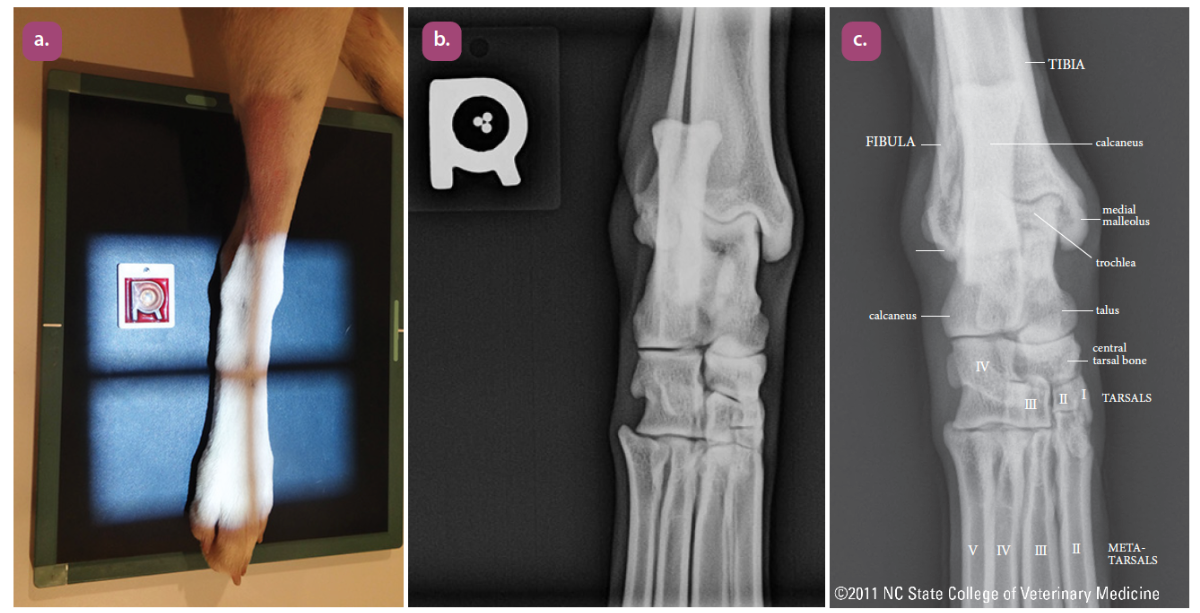

dorsoplantar projection of the tarsus